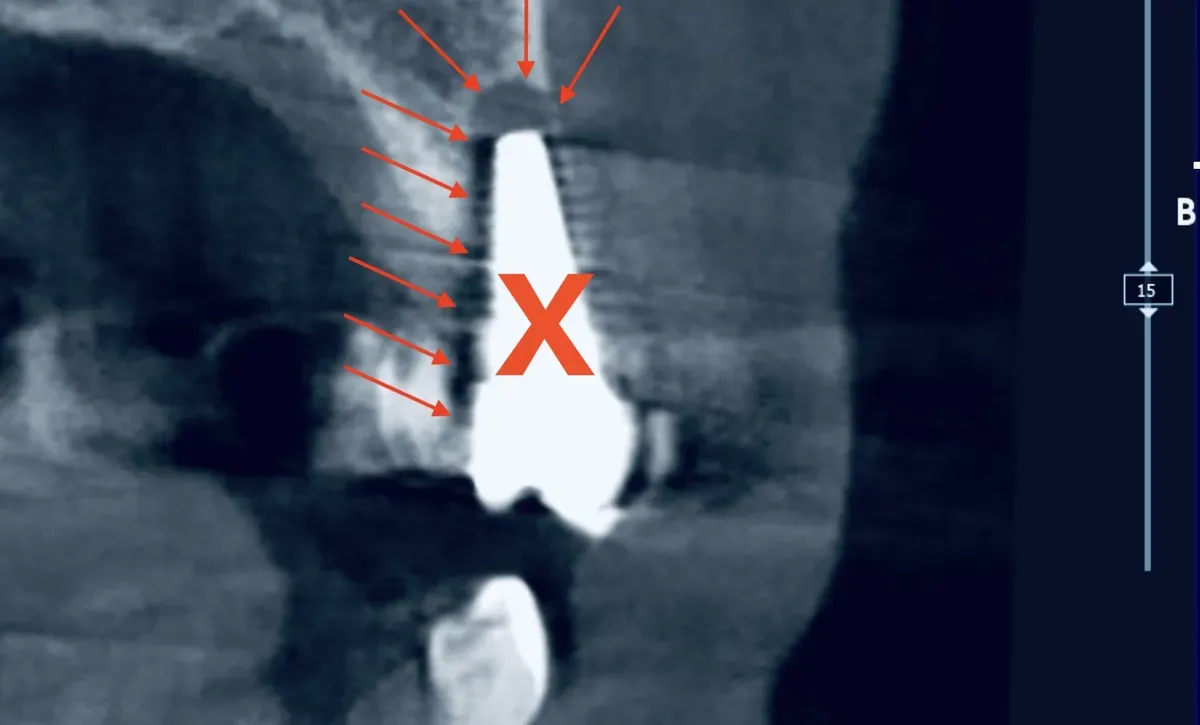

CBCT di un impianto dentale fallito con perdita ossea peri-implantare